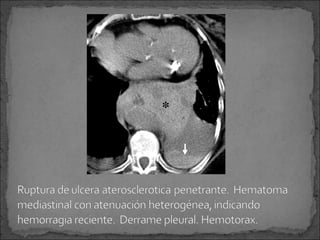

Ulceración de una placa ateromatosa que ha erosionado

la capa interna, alcanzando la capa media y produciendo

un hematoma en la media.

Se puede complicar con: aneurisma o ruptura.

Si existe ruptura o hemorragia mediastinal, es imposible

diferenciar entre una ruptura de aneurisma o una

complicación de ulcera aterosclerótica.

En ambos casos:

 Tratamiento es quirúrgico.